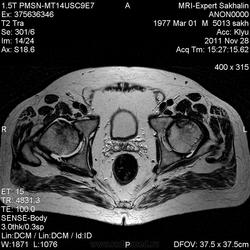

Тазобедренные суставы.МРТ.

Мне сообщил, что  в поликлинике по месту жительства патологию не нашли, в другой поликлинике заподозрили ДОА.

Хромает на правую ногу,беспокоят боли в тазобедренных суставах около полугода или больше.Это вся информация.

асептический некроз головок бедренных костей (более выражена картина справа)

nnemo, я написала "аваскулярный некроз"-может быть, это более корректно, нет?